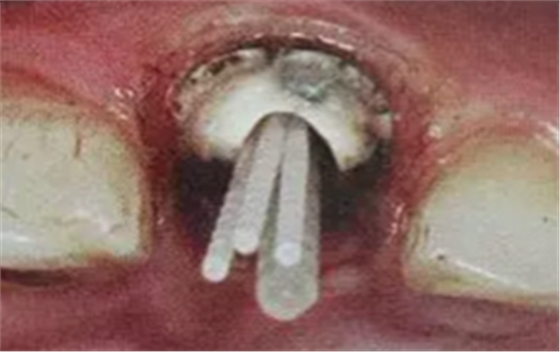

13. 不規(guī)則根管的纖維樁粘接

普通纖維樁對(duì)圓形截面的根管適合性較好,面對(duì)不規(guī)則時(shí)(橢圓形、喇叭形等)根管適應(yīng)性差,難以取得好粘接和修復(fù)效果。

輔樁的運(yùn)用

輔樁的運(yùn)用可改善這些適應(yīng)性的問題

(ELLIPSON 技術(shù))

(超聲預(yù)備根管完成)

ELLIPSON 技術(shù),采用超聲預(yù)備鉆對(duì)扁圓形根管進(jìn)行直接預(yù)備,改善了樁核根管的適應(yīng)性。有效的保存了根管牙體組織,從而增強(qiáng)了粘接面積,,減少樹脂水門汀的厚度,提高根管內(nèi)纖維樁的粘接強(qiáng)度。

(插入橢圓形纖維樁)